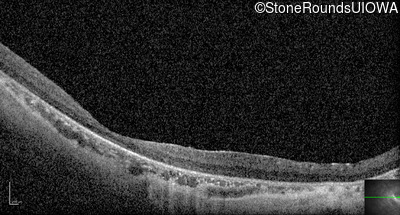

Optical Coherence Tomography - Left - 10/350 sc

Exemplar / OCT Stack